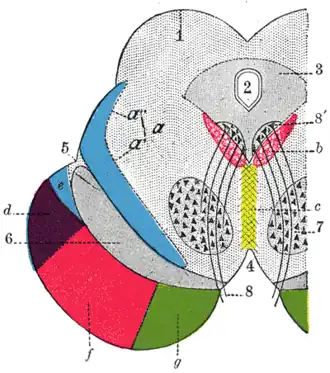

Coronal section through mid-brain. ("e" is Portion of medial lemniscus, which runs to the lentiform nucleus and insula. "a’" is also the medial lemniscus.) | |